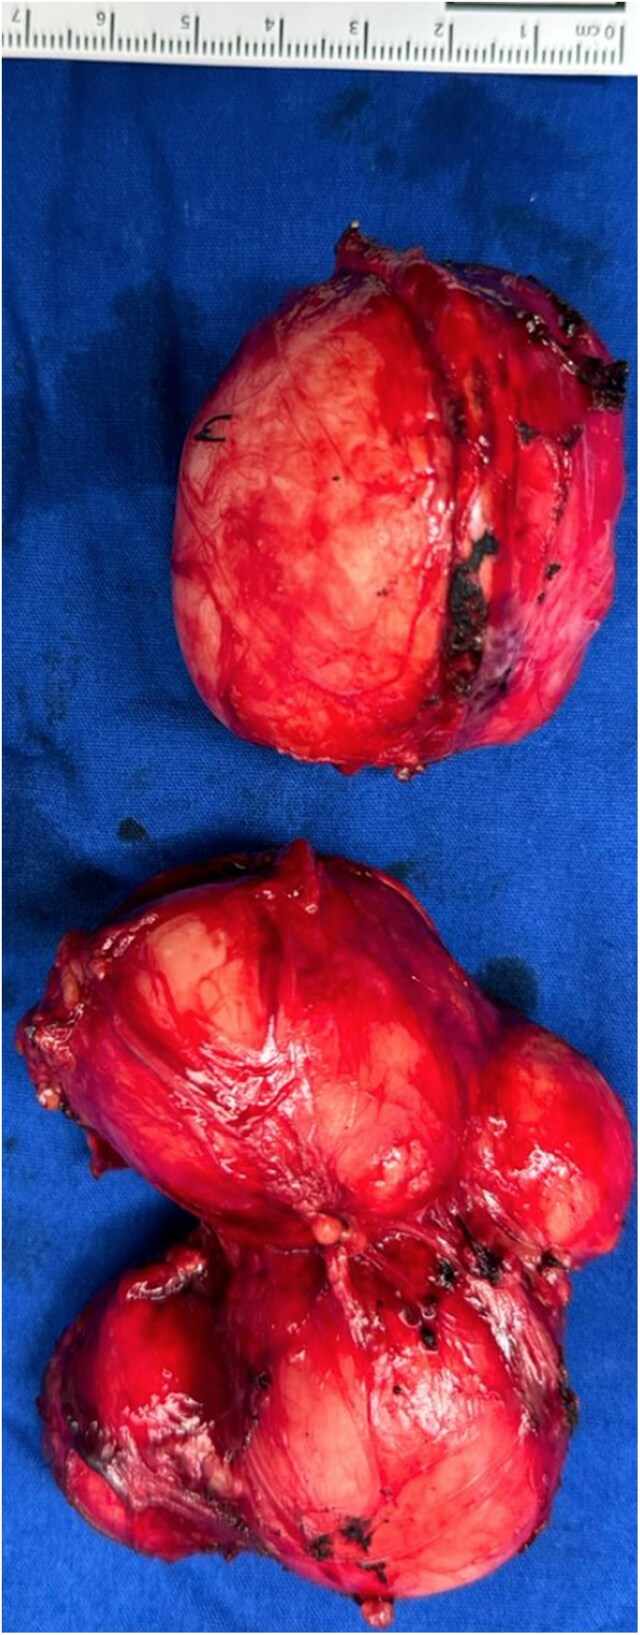

Adrenal leiomyomas are rare, benign tumors originating in the adrenal glands. They have a varied age of presentation, occur with a slight female predominance, and are typically unilateral, although bilateral cases can occur. Symptoms typically include abdominal or flank pain. This report presents a rare case of an 11-year-old male with disseminated molluscum contagiosum, diagnosed with bilateral adrenal leiomyomas. Imaging revealed large, heterogeneous adrenal masses, and the patient underwent successful adrenalectomy. This case underscores the rarity of adrenal leiomyomas in the pediatric population and highlights the critical role of imaging and surgical intervention in their management.